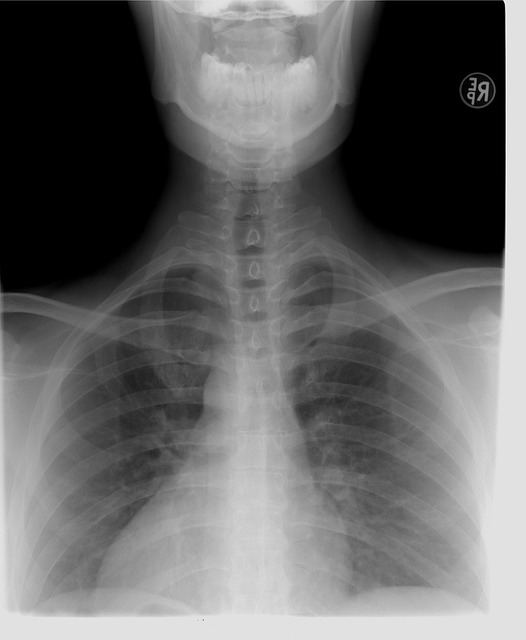

Stalo se vám někdy, že jste měli opravdu veliké problémy se zády, že vás bolela tak moc záda, že jste ani nemohli chodit? V tom případě je nejlepší, pokud také budete cvičit opravdu kvalitní a speciální cviky proti bolestem zad. Také je opravdu ale velice výhodné, pokud si zjistíte informace, proč vás bolí záda, jestli třeba nemáte vrozenou skoliózu. Nebo jestli nemáte například i vyhřezlou ploténku? Podle mého názoru by bylo nejlepší, kdybyste si zašli k nějakému lékaři nebo specialistovi, který vám všechno řekne. Co vás trápí nebo co byste měli dělat?

Samozřejmě, že pokud máte vyhřezlou ploténku, tak na to také pomáhá operace, ale také nezapomeňte, abyste dále pokračovali v tom, abyste cvičili a tak podobně. Pokud máte skoliózu páteře, tak ve většině případů operace tady vůbec nefunguje. Při skolióze páteře se operace ani nedoporučuje, protože si myslím, že to vůbec nemá žádný efekt. Proto si myslím, že když budete mít skoliózu páteře tak je nejlepší, pokud budete cvičit nějaké speciální cviky, a to včetně toho i kdybyste měli vyhřezlé ploténky a tak podobně, protože po operaci vyhřezlé ploténky pravděpodobně budete chodit i na rehabilitace a tak dále.